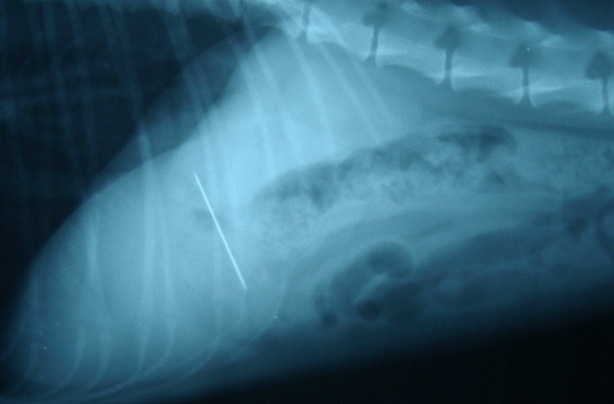

川越市のマリー動物病院◆跛行をしめし、来院した大型犬

①外科切除 と ②抗癌治療

骨肉腫と診断され、手術にて断脚後に抗癌治療を行う。

その後、1年生活して天寿を全うしました。